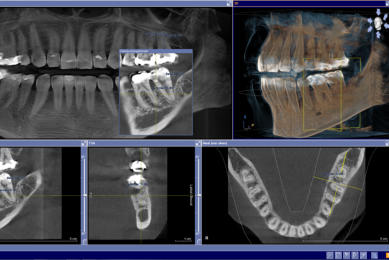

Für den Zahnarzt haben Röntgenaufnahmen einen unverzichtbaren Stellenwert in der Diagnostik und Behandlungsplanung. Für die Implantologie und viele andere zahnärztliche Bereiche bietet das digitale Röntgen eine optimale Möglichkeit der Vorplanung und Unterstützung während der Behandlung. Digitale 2D-Röntgenbilder und DVT´s/ 3D-Röntgenbilder können wir in besonders hoher digitaler Qualität und geringer Strahlendosis durchführen.

3D- Röntgen - DVT